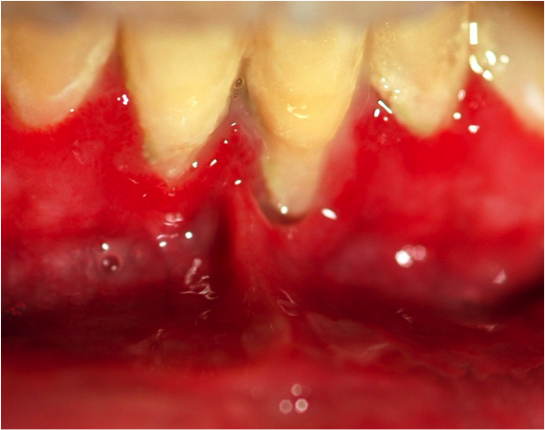

PUN evocatrice du VIH